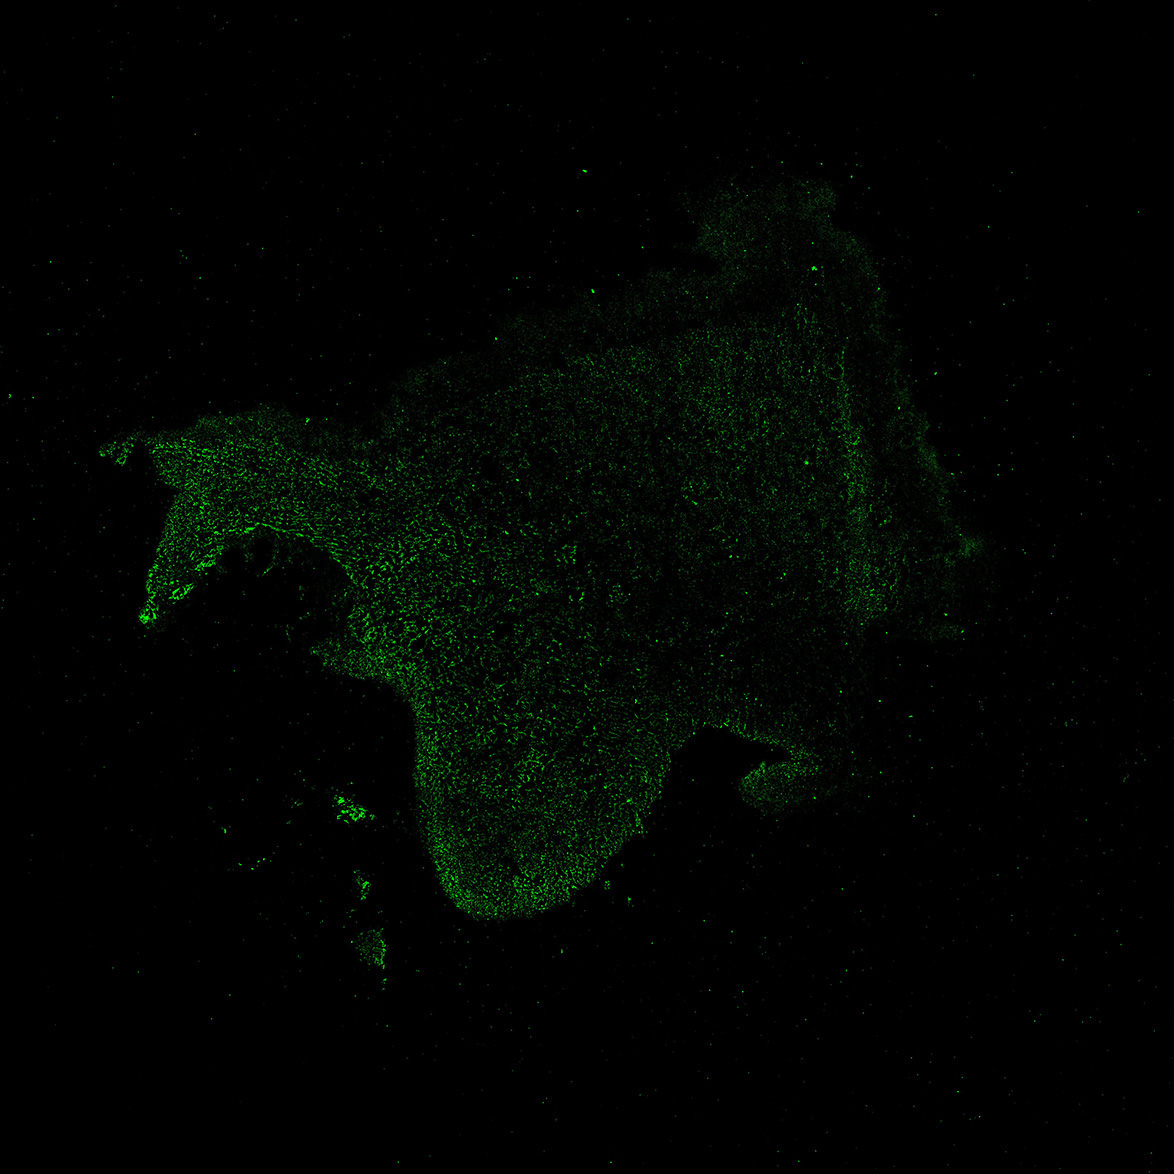

TH

6PCW human midbrain